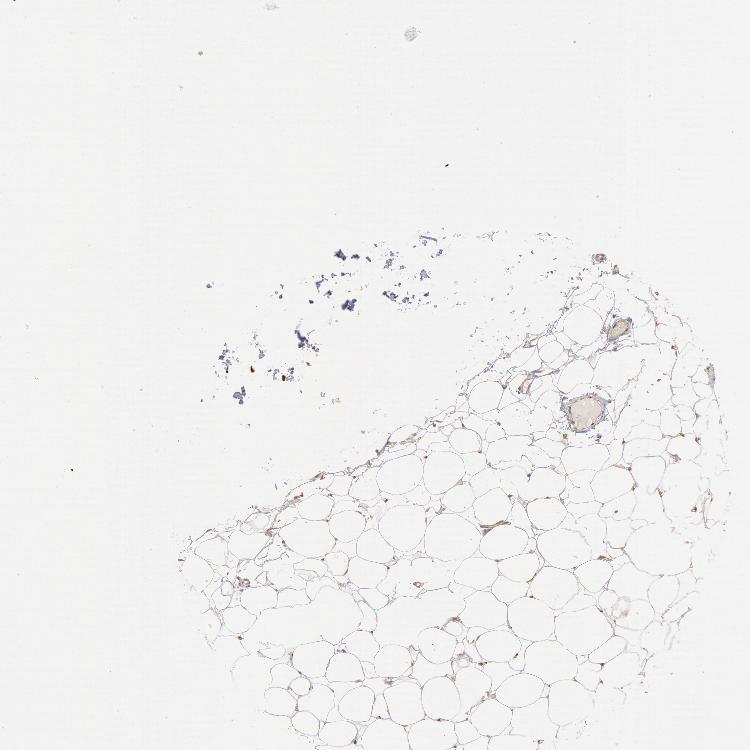

SOFT TISSUE 1 - Antibody stainingi

Antibody staining in the annotated cell types in the current human tissue is reported as not detected, low, medium, or high, based on conventional immunohistochemistry profiling in selected tissues. This score is based on the combination of the staining intensity and fraction of stained cells.

Each image is clickable and will lead to virtual microscopy that enables deeper exploration of all samples and also displays staining intensity scores, fraction scores and subcellular localization as well as patient and tissue information for each sample.

Antibody HPA001318

Fibroblasts Medium

Peripheral nerve Not detected